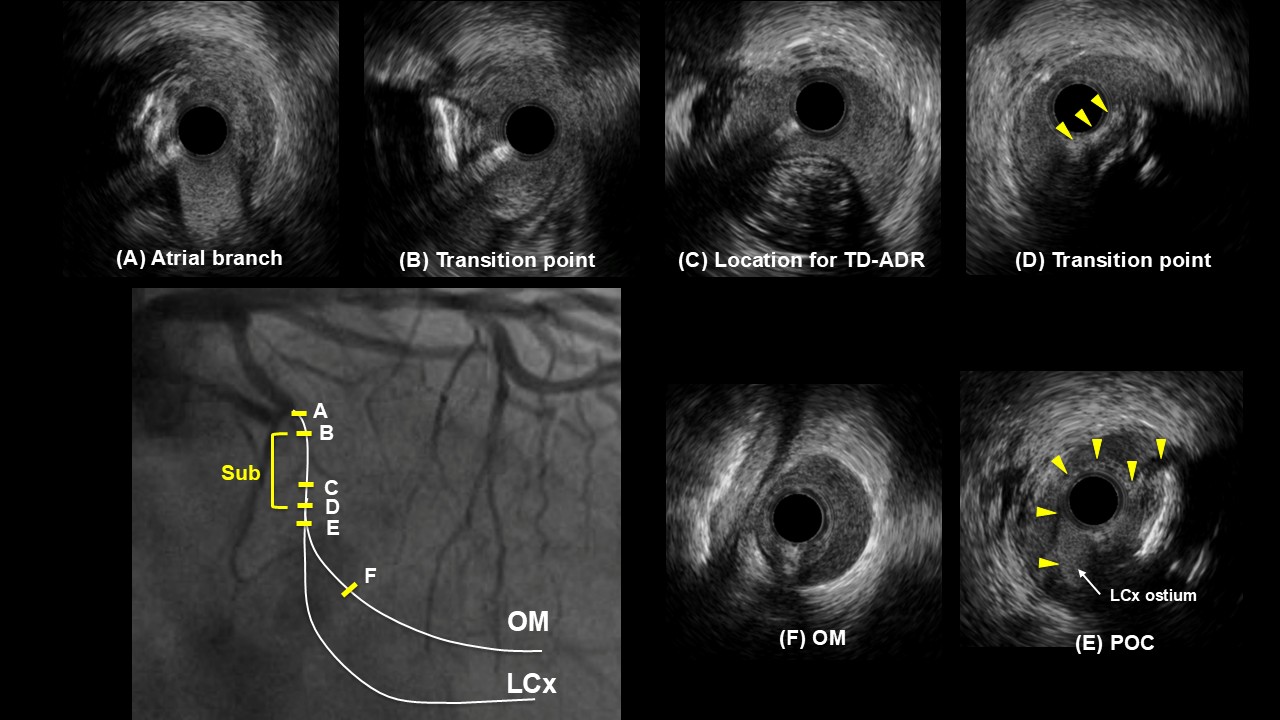

IVUS pullback from the OM showed a short segment of subintimal tracking before the LCX–OM bifurcation and a large hematoma from the bifurcation extending into the distal OM. Further wiring toward the distal LCX was attempted, and IVUS confirmed that the wire was located in the false lumen. The IVUS catheter was left in place within the false lumen to serve as a landmark. A second guiding catheter was then positioned, and using real-time IVUS guidance, a new wire was advanced from the second guiding catheter into the true LCX lumen across the bifurcation.

After true lumen access was achieved, provisional LCX to OM stenting restored TIMI 3 flow. Final IVUS showed good stent expansion and apposition, without edge dissection or residual hematoma.